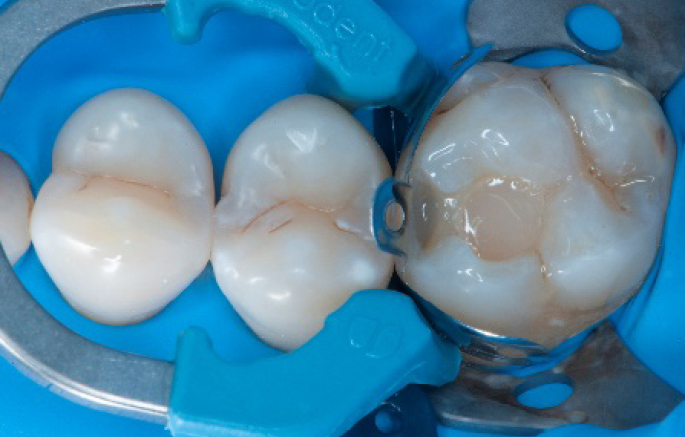

Step 4:

The complete Palodent1 system in place: sectional matrix, wedge and ring.

Step 5:

Buccal view of the Palodent1 system.

Transformation of class II into class I, restoring the interproximal wall with Spectra ST4 composite in shade A2.

Step 9:

Transformation of a big class I into a small class I, using SDR® flow+ material in one increment up to 4 mm.

Step 10:

The situation after the application of SDR® flow+ material.

Step 11:

Occlusal surface restored using Spectra ST4 composite in shade A2.